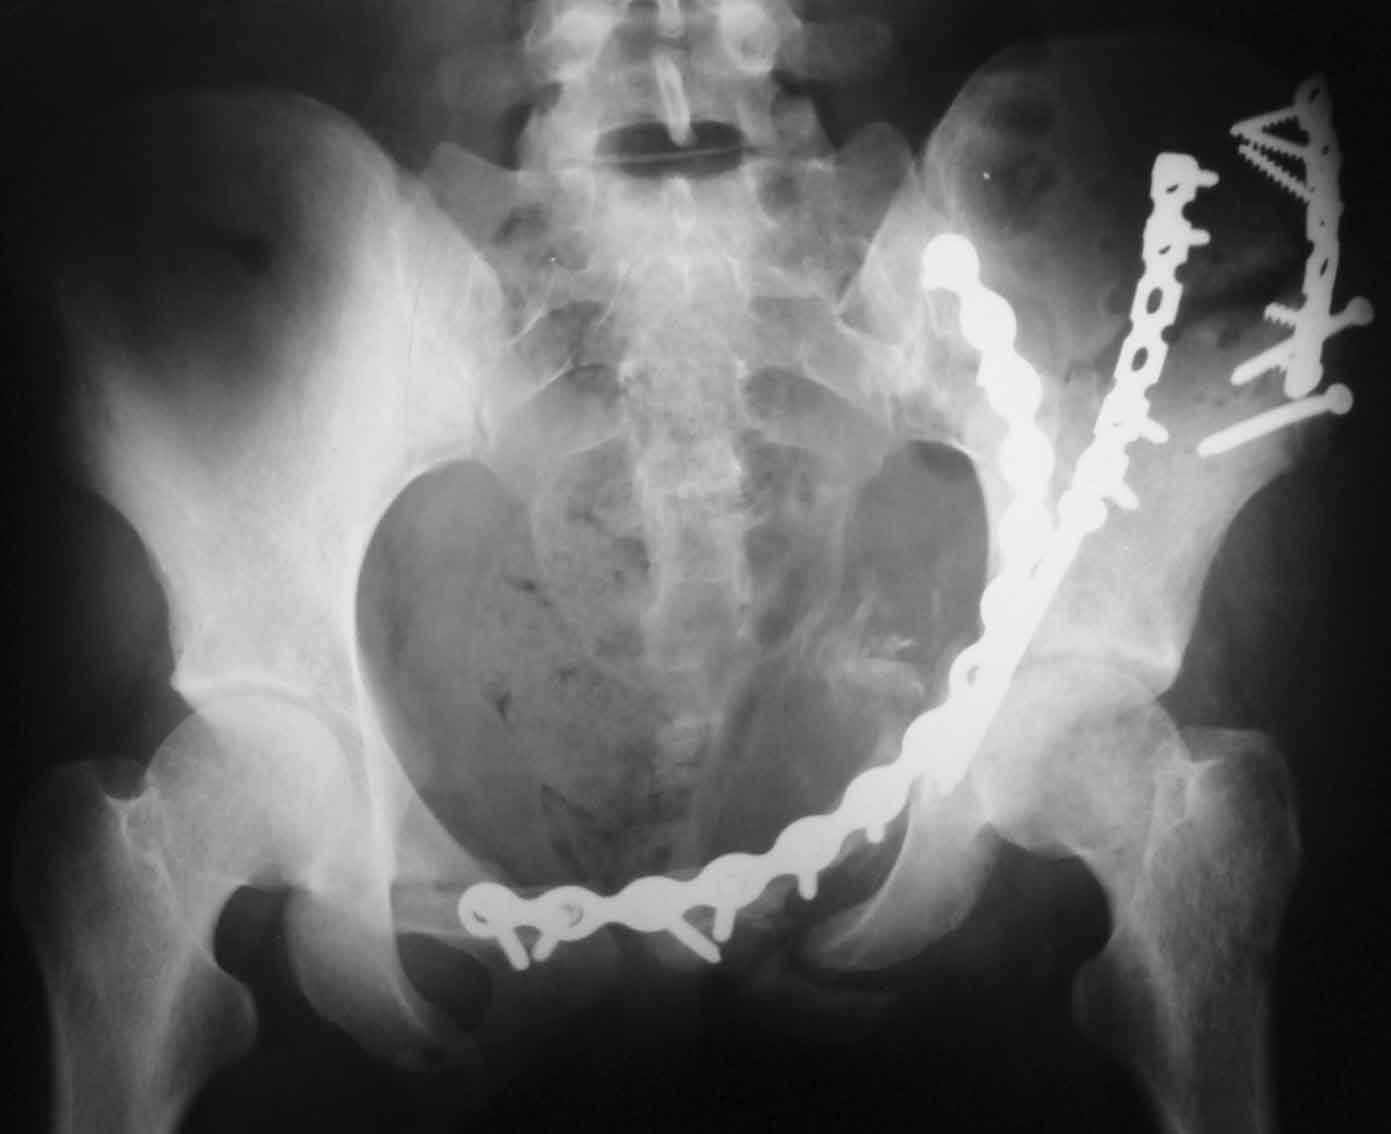

Прямая проекция

По всей видимости, вы имеете в виду канюлированный винт, который проецируется на вертлужной впадине. Та вот, он проведен не через лонную, а седалищную кость. Вертлужная впадина абсолютно интактна. Это хорошо видно на проекции inlet.